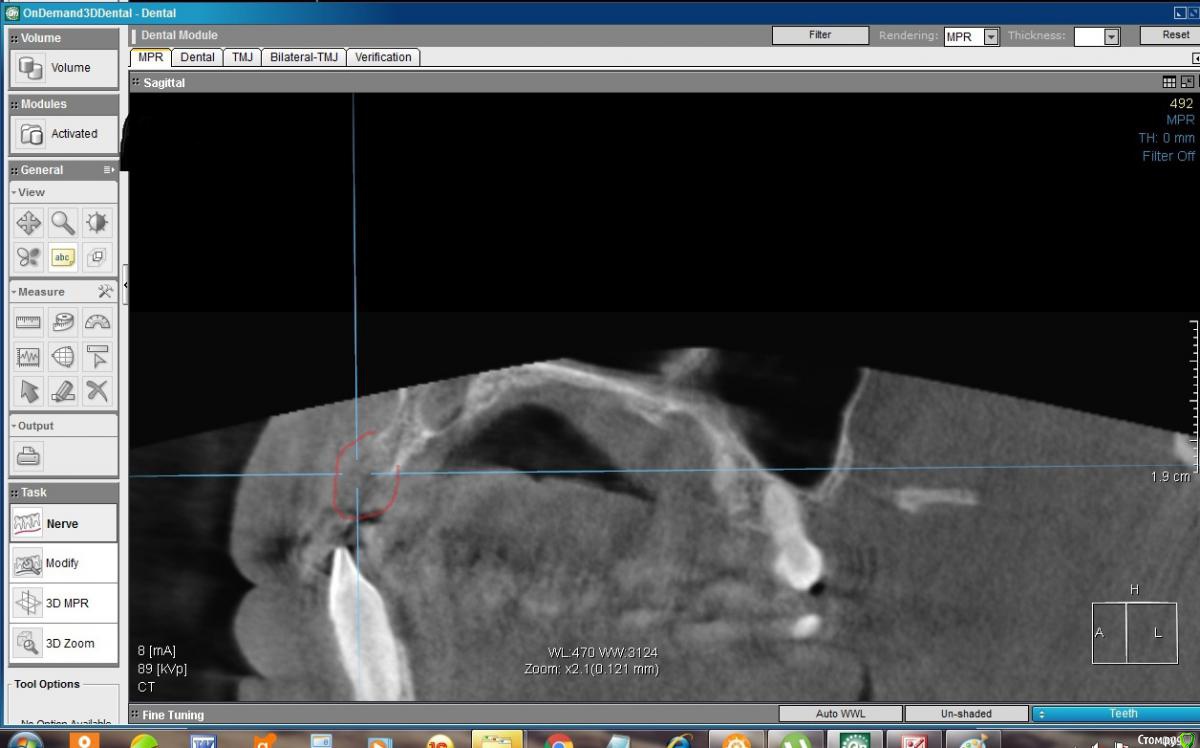

konst2009 Опубликовано 26 августа, 2019 Поделиться Опубликовано 26 августа, 2019 Здравствуйте.Два с половиной месяца назад удалил верхние передние 4 зуба. Вчера сделал KT. В сагиттальной проекции на месте лунок удаленных зубов вместо ожидаемой костной ткани как будто пустота, где-то даже губная пластина не просматривается. Срезы между лунками: Такое разве пригодно для имплантации? Что делать, ждать? Ссылка на комментарий

konst2009 Опубликовано 27 августа, 2019 Автор Поделиться Опубликовано 27 августа, 2019 Здравствуйте! После удаления зуба,объём костной ткани неминуемо уменьшается,чем больше времени после удаления-тем меньше костной ткани останется Понятно, но в лунках, если я правильно понимаю, после удаления сначала образовывается кровяной сгусток, а потом костная ткань, а ее почему-то на КТ не видно, как будто там пустота, как это можно объяснить? Ссылка на комментарий

колесников Опубликовано 27 августа, 2019 Поделиться Опубликовано 27 августа, 2019 Слабоминерализованая,потому не контрастируется Ссылка на комментарий